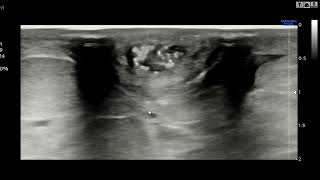

3. УЗИ матки: Ультразвуковое исследование может использоваться для обнаружения изменений в матке или ее окружающих тканях. Этот метод может быть полезным в выявлении опухолей или аномалий.